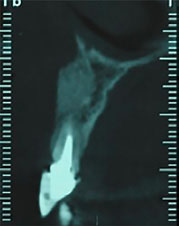

After eight months, the grafted site healed without any complications. A CBCT view showed a favorable reconstruction of the grafted area (Figure 4). Local anesthesia with 2% lidocaine (1:100,000 epinephrine) was delivered. Without flap elevation, the lateral incisor was extracted atraumatically using a periotome. The extraction socket was thoroughly curetted for complete debridement of the granulation tissue and then irrigated with normal saline solution. Osteotomy site preparation was performed, and a self-threaded titanium implant (3.75×11.5 mm, Osseotite®, Biomet 3i, Florida, United States) was inserted at the extraction socket. Insertion torque value was 40 N/cm2, and favorable primary stability was achieved from the residual alveolar bone. The implant platform was placed 2 mm apical to the cementoenamel junction of the right maxillary central incisor (Figure 5A). The gap between the implant surface and the labial wall of the socket was filled with xenograft particles (cerabone®, Botiss Biomaterials GmbH, Zossen, Germany).

Figure 4.

The CBCT view of the grafted site after 8 months.